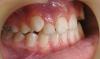

Alin Alexandr Опубликовано 18 мая, 2011 Поделиться Опубликовано 18 мая, 2011 (изменено) Добрый день!Меня зовут Александр, мне 30 лет. У меня дефект прикуса в виде двух неправильно растущих верхних резцов (похож на вампира ). В силу возраста и других причин, брекеты носить не хочу и не буду. Хочу зубы просто удалить и всё. Вопрос, можно ли это сделать? Или удаление верхних резцов повлечёт за собой какие то последствия для челюсти в целом?Фото прилагаю (фото открытого рта с зубами не моё, но ситуация аналогична. Рентген мой): Спасибо! P.S. Возможно на форуме уже есть аналогичные темы. Но по причине своей безграмотности в данном вопросе, воспользоваться поиском я не смог (не знаю что искать). За ссылки на соотв. ветки буду благодарен. UPD: прошу прощения, в теме неверно указал зубы (видимо всётаки не клыки, а верхние резцы) Изменено 18 мая, 2011 пользователем Alin Alexandr Ссылка на комментарий

Alin Alexandr Опубликовано 19 мая, 2011 Автор Поделиться Опубликовано 19 мая, 2011 что значит зубы опрокинутся? зубы не кегли. Но повышенная нагрузка на резцы и премоляры (которые будут вынуждены заменять собой клык) приведет к их ранней потере либо к повышенному стиранию.Клык незаменимый зуб. А если для того чтобы поставить их на место нужно вырвать от двух до четырёх соседних зубов? Это приведёт к в свою очередь уже к повышенному истиранию клыков, я правильно понимаю? Оба зуба, кстати вот в таком состоянии: К слову, я их не запускал - на соседних ничего такого пока нет. Ссылка на комментарий